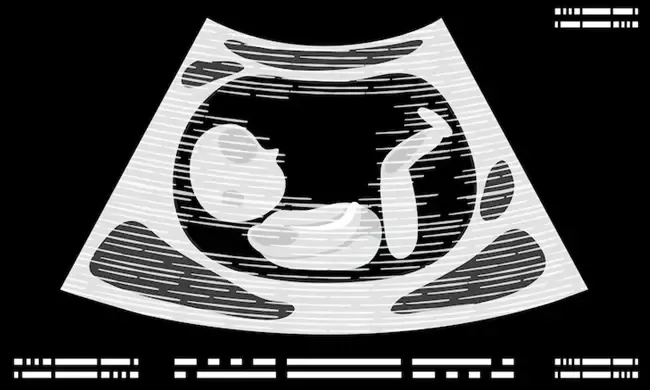

นอกจากการอัลตร้าซาวด์ การนับลูกดิ้นช่วยให้รู้ถึงเจริญเติบโตของทารก